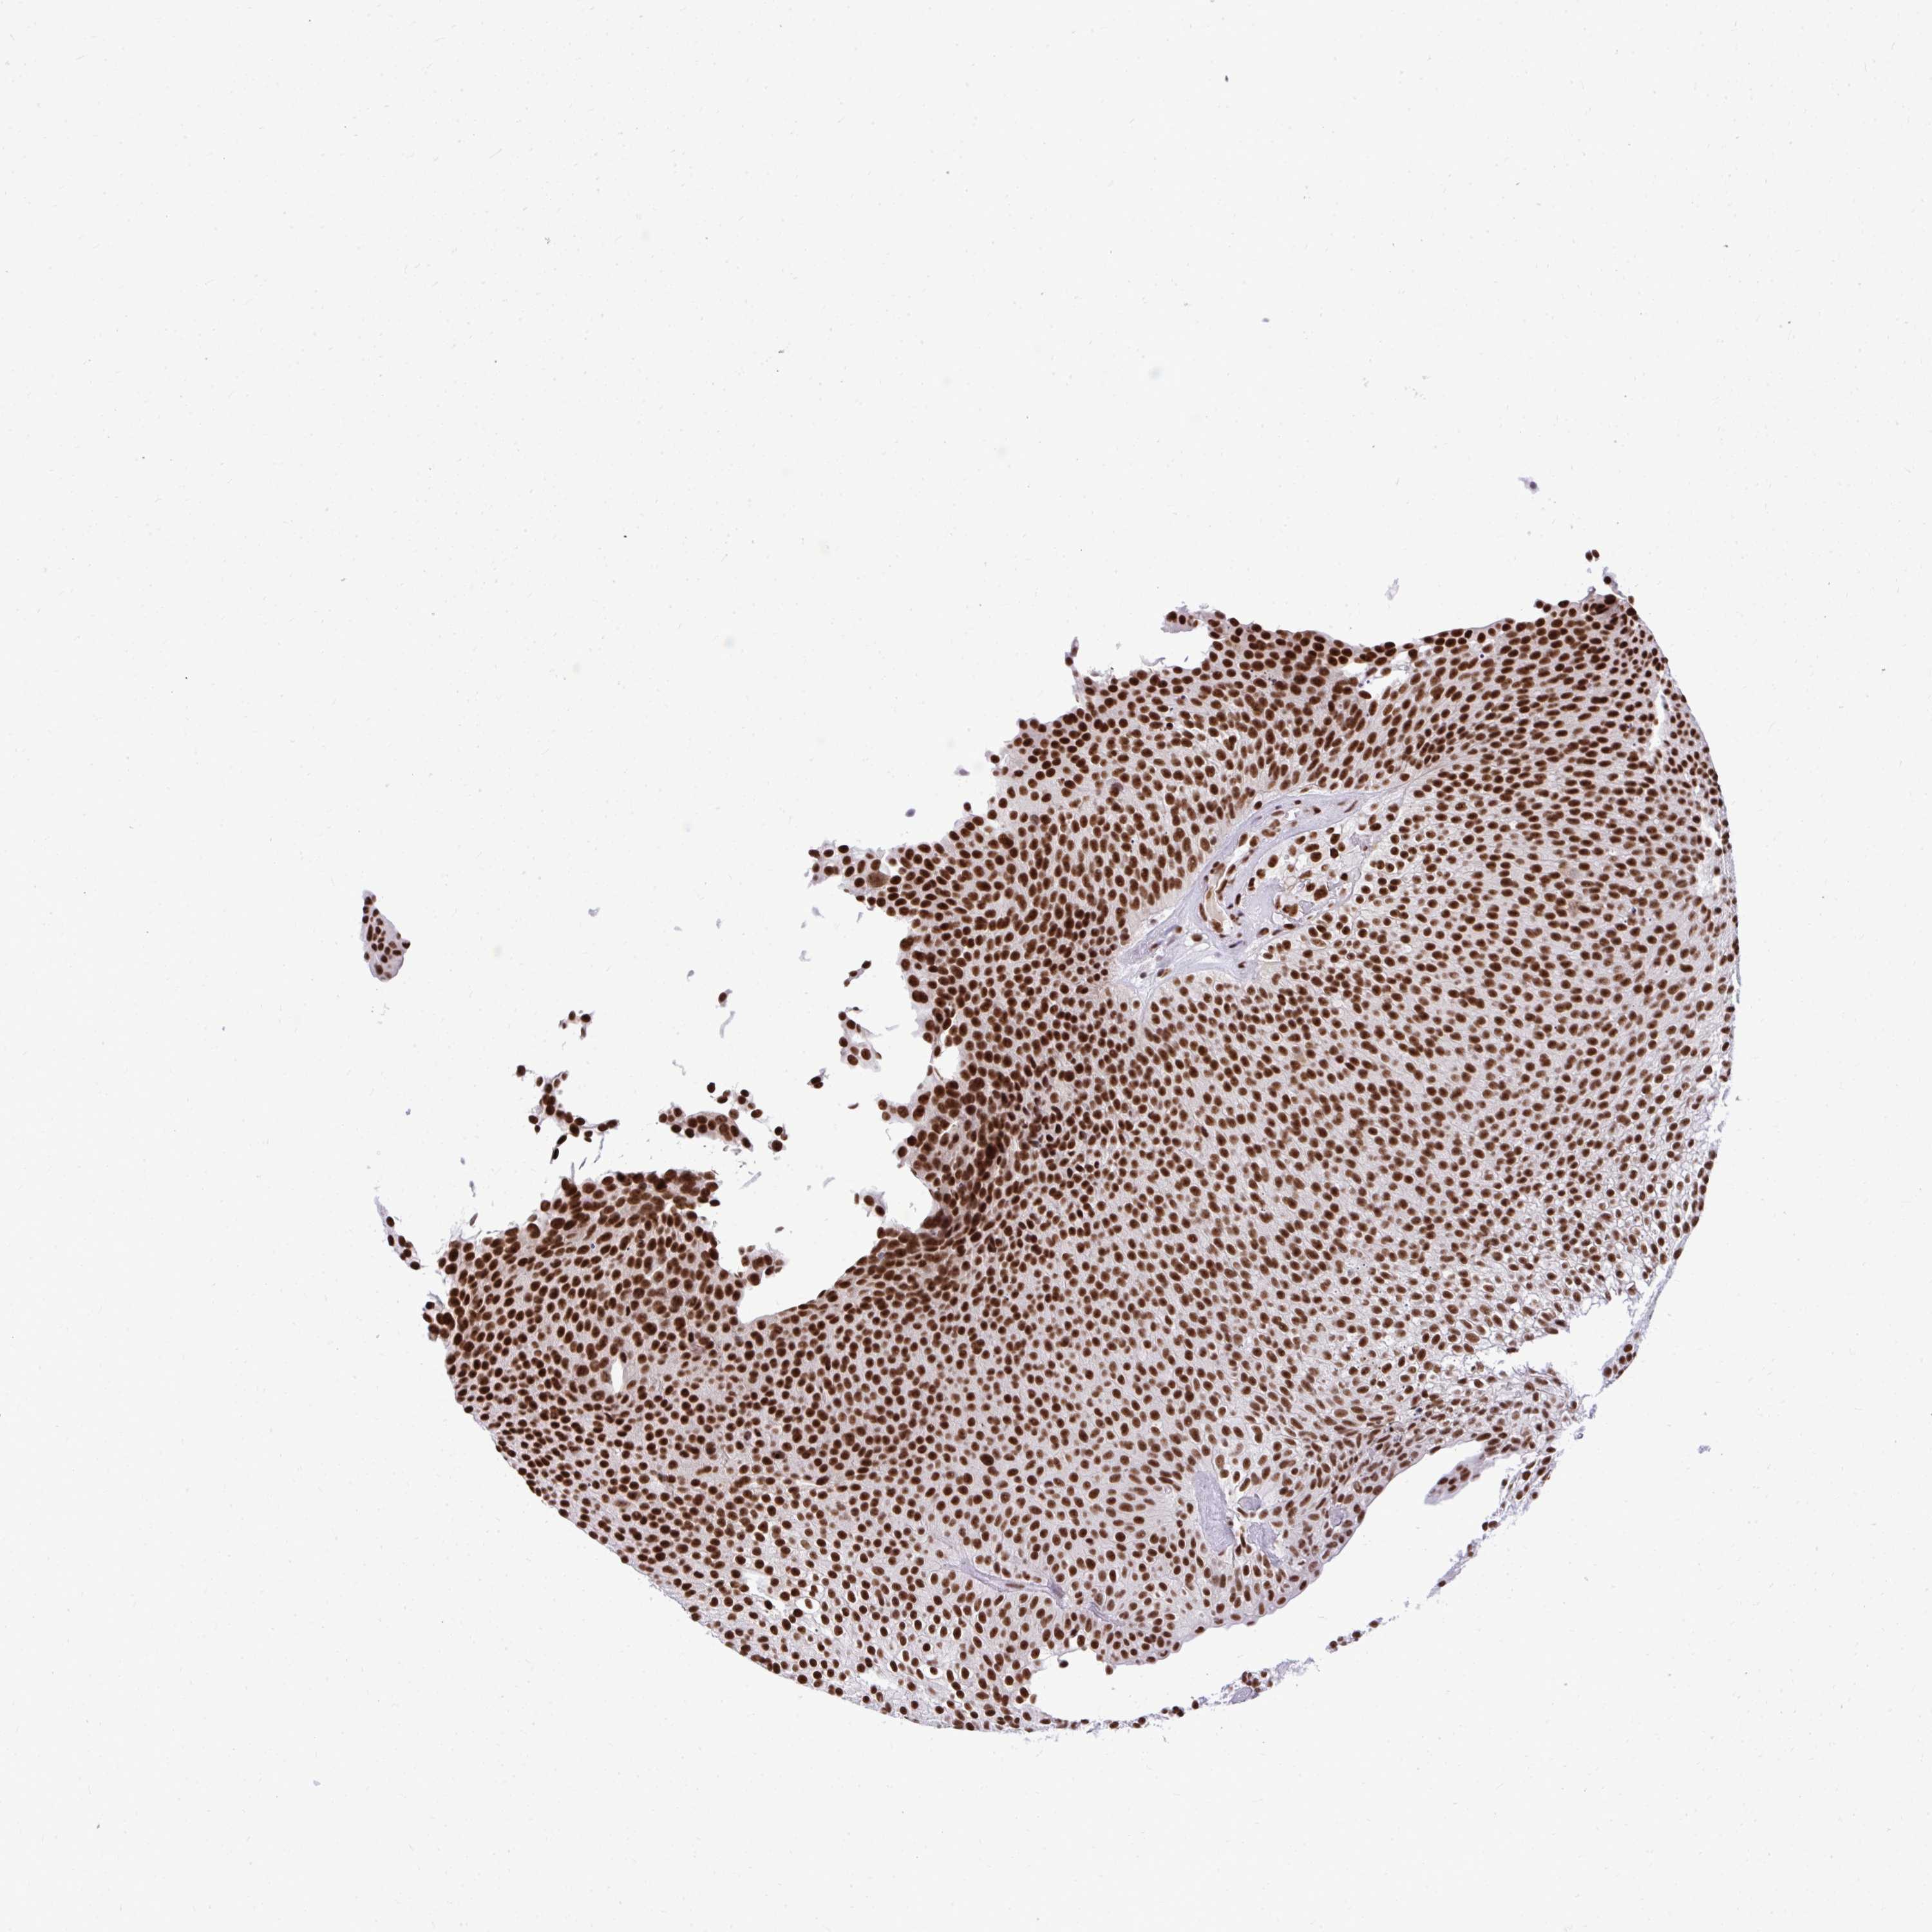

UROTHELIAL CANCER - Protein expressioni

A mouse-over function shows sample information and annotation data. Click on an image to view it in a full screen mode. Samples can be filtered based on level of antibody staining by selecting one or several of the following categories: high, medium, low and not detected. The assay and annotation is described here.

Note that samples used for immunohistochemistry by the Human Protein Atlas do not correspond to samples in the TCGA dataset.

Antibody stainingi

Antibody staining in the annotated cell types in the current human tissue is reported as not detected, low, medium, or high, based on conventional immunohistochemistry profiling in selected tissues. This score is based on the combination of the staining intensity and fraction of stained cells.

Each image is clickable and will lead to virtual microscopy that enables deeper exploration of all samples and also displays staining intensity scores, fraction scores and subcellular localization as well as patient and tissue information for each sample.

Antibody HPA038051

Antibody HPA059070

Antibody CAB012448

Staining

High

Medium

Low

Not detected

Intensity

Strong

Moderate

Weak

Negative

Quantity

>75%

75%-25%

<25%

None

Location

Nuclear

Cytoplasmic/membranous

Cytoplasmic/membranous,nuclear

Urothelial carcinoma, High grade

Urothelial carcinoma, Low grade

Urothelial carcinoma, NOS